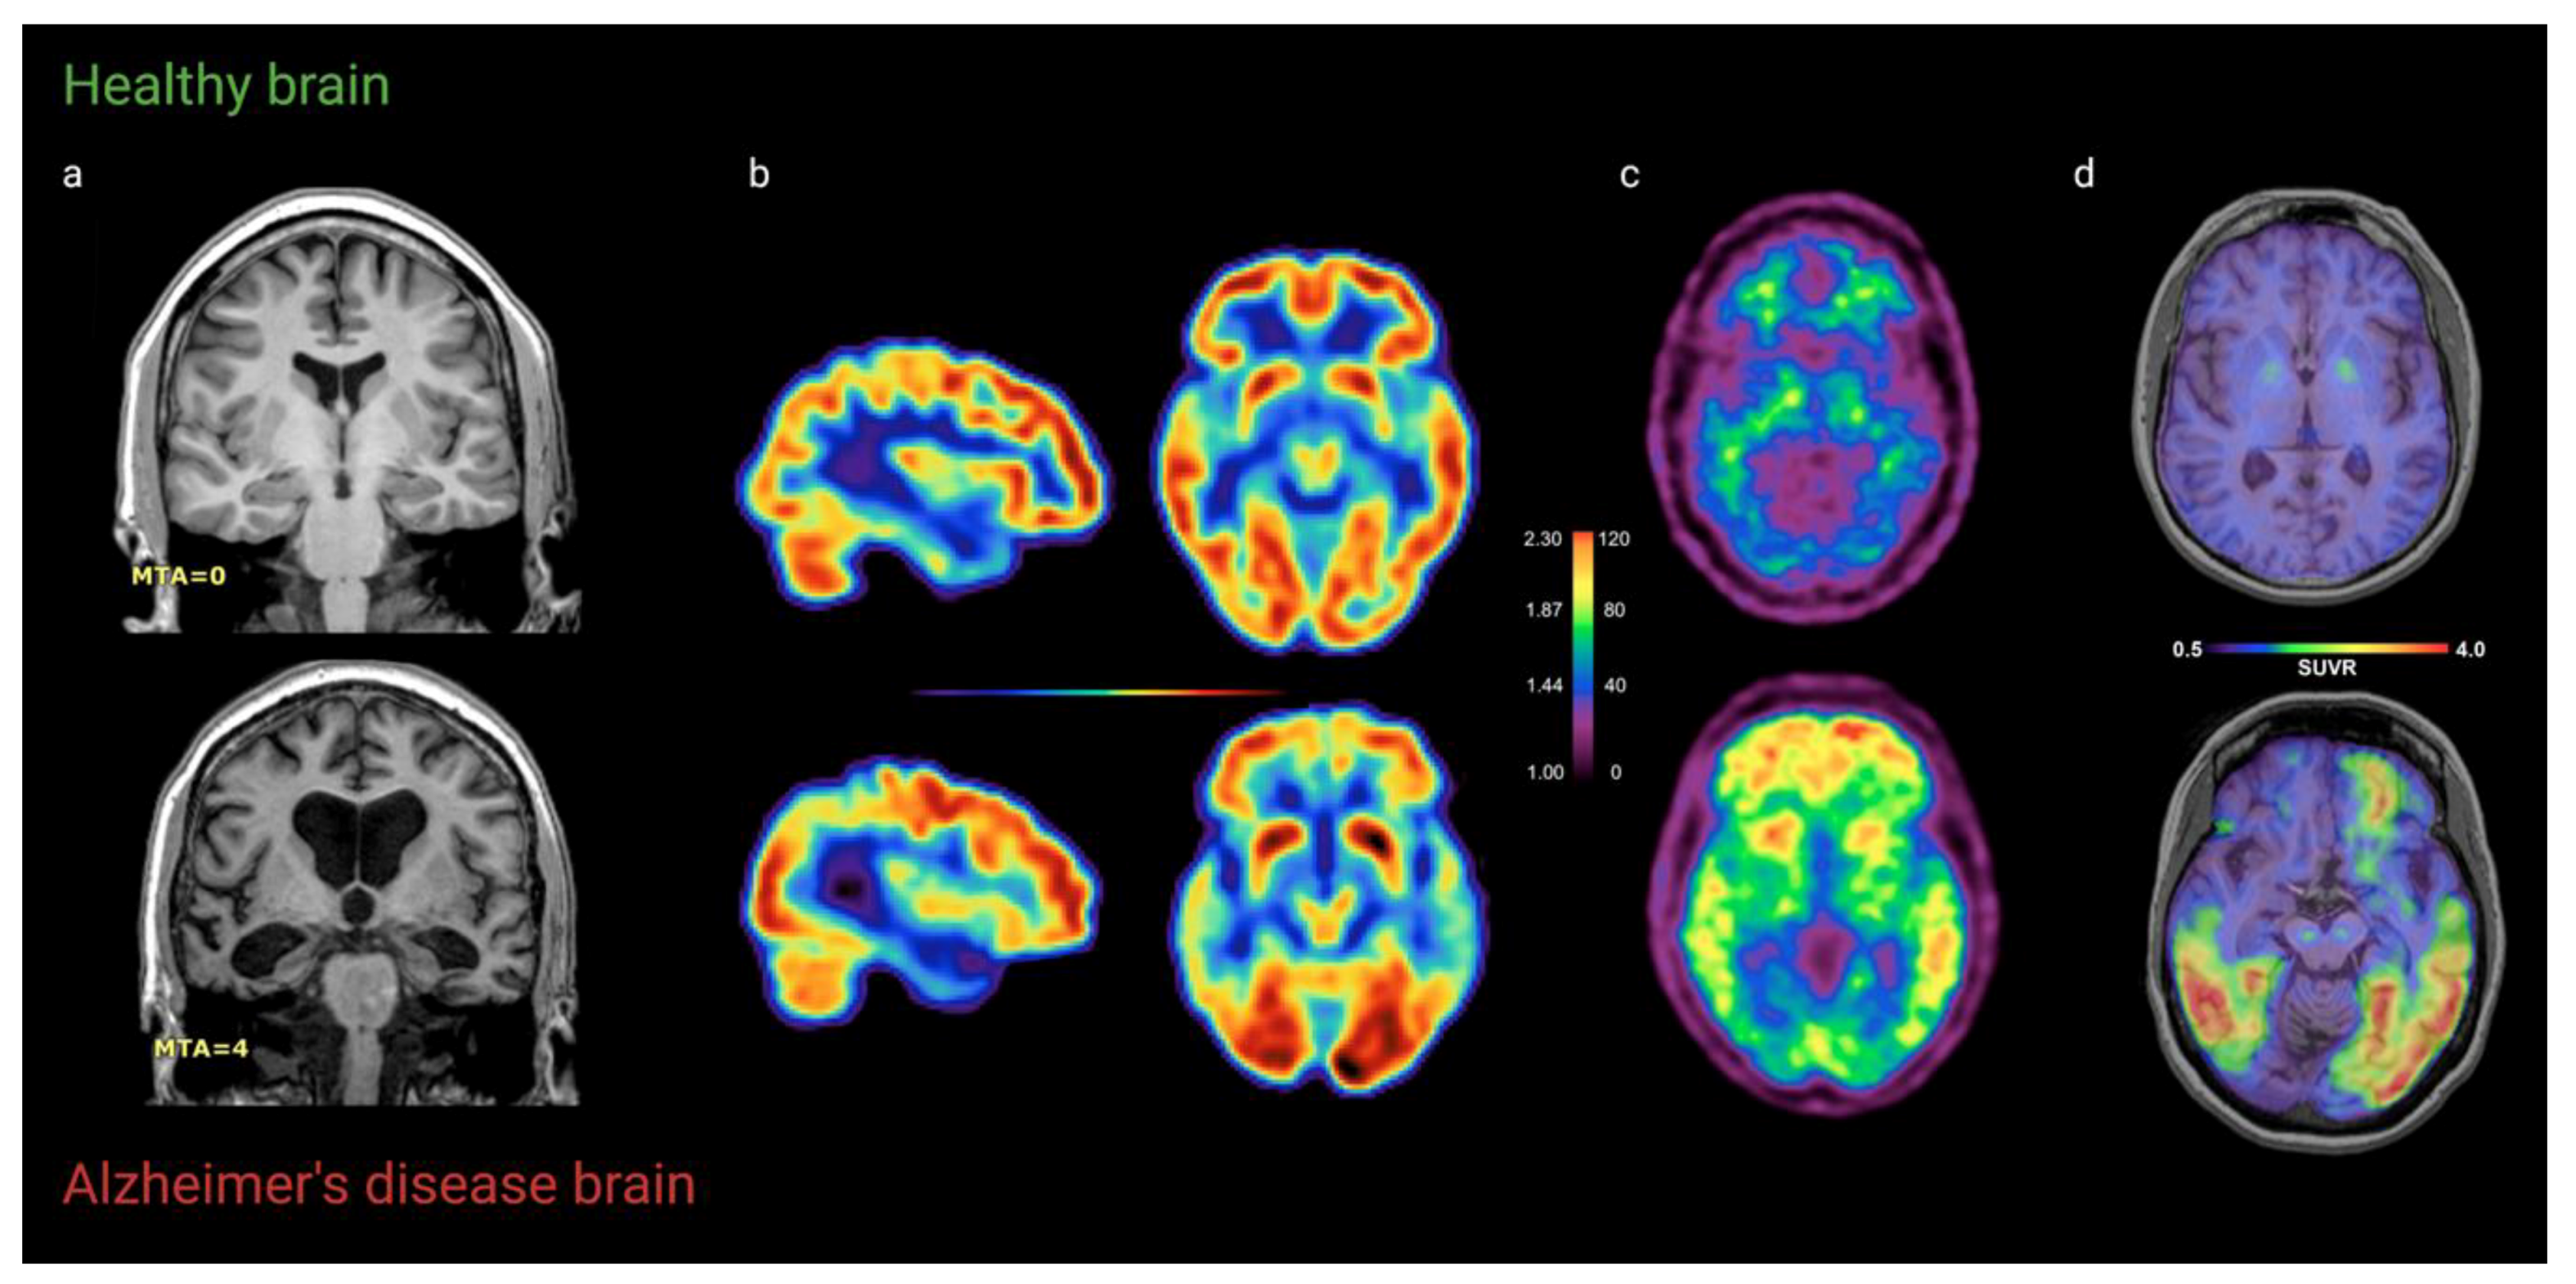

2.1.2. Findings

2.2. FDG-PET

2.2.2. Findings

2.3. Amyloid-PET

2.3.2. Findings

2.4. Tau-PET

2.4.2. Findings